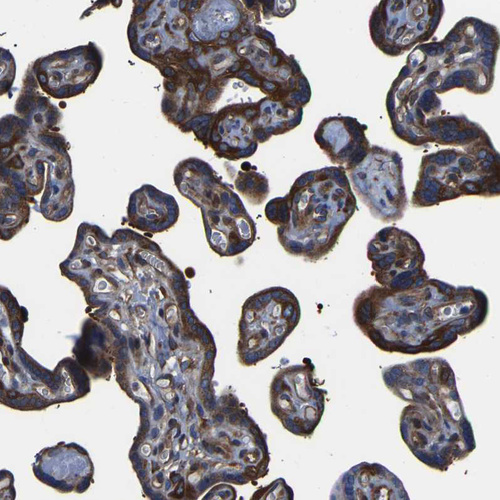

Immunohistochemical staining of human placenta shows strong cytoplasmic positivity in trophoblastic cells.